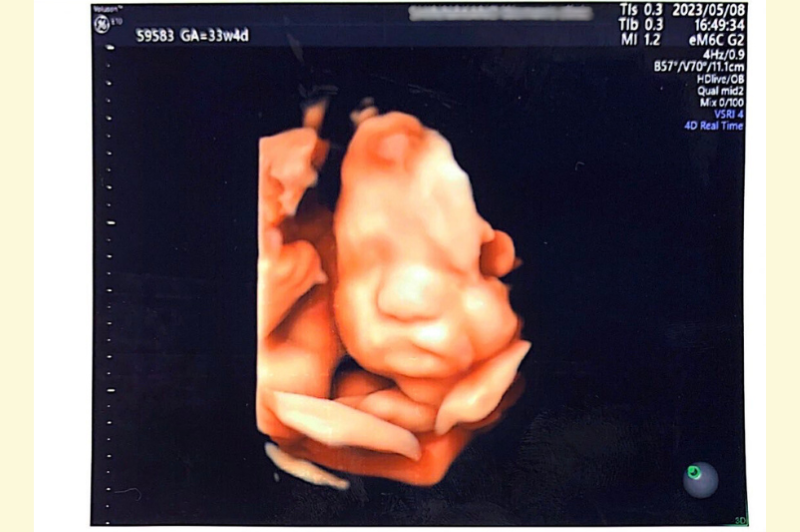

「お母さんになれました」